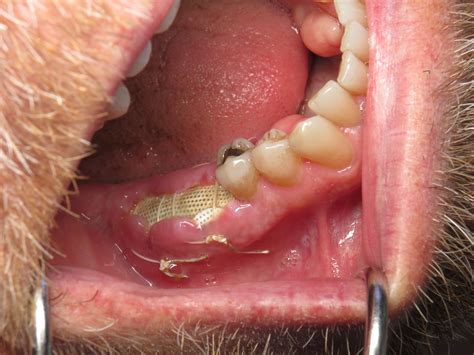

The process of placing a bone graft after tooth extraction is typically performed during the same appointment as the extraction itself. Once the tooth is removed, the dentist cleans the socket thoroughly to ensure no infection remains. The grafting material is then carefully packed into the space. A membrane is often placed over the site to hold the graft in place and protect the area from soft tissue ingrowth, ensuring the bone has the best chance to mature.

A bone graft after tooth extraction, often referred to as "socket preservation," serves as a scaffold for your body to grow new, healthy bone. By filling the empty socket with grafting material, your dentist creates a environment that encourages your natural bone cells to regenerate and integrate with the graft, effectively stopping the bone loss process before it starts.

• Alloplasts: Synthetic materials, such as bioactive glass or hydroxyapatite, which are designed to stimulate natural bone growth.